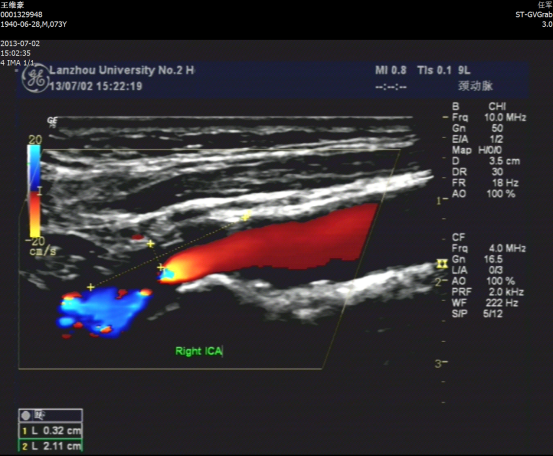

术前颈动脉超声

术前